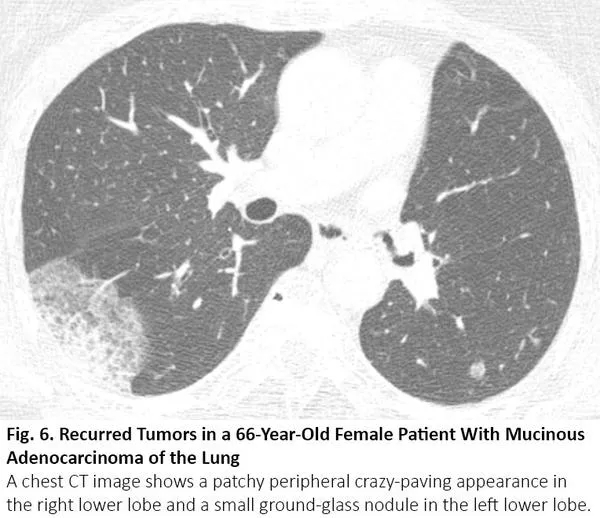

COVID-19的胸部CT可伴有局部的实质化和网状阴影(铺路石征影像表现)或其他组织性肺炎的表现,如反晕征。17% - 20%的COVID-19患者的CT与各种感染性、非感染性肺部疾病(如超敏性肺炎、肺孢子虫肺炎和弥漫性肺泡出血)难以区分(图2)。

图2. 一位67岁女性患者的胸部CT呈现COVID-19不典型特征